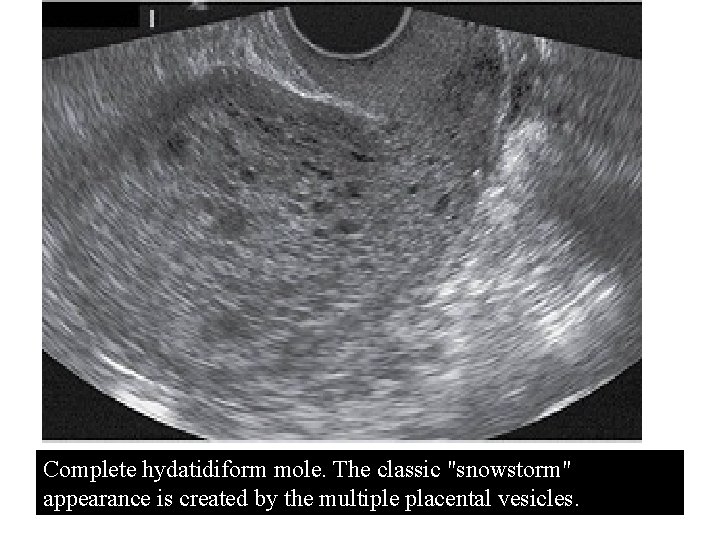

How Is Complete Mole Diagnosed? U/S is helpful in making a pre-evacuation diagnosis but the definitive diagnosis is made by histological examination. U/S: Early detection reduced from 16 weeks (passage of vesicles) to 12 ws βh. CG levels > 2 multiples of the median may be of value in the diagnosis RCOG Guideline No. 38 ; 2010

U/S& βh. CG Definite diagnosis on first U/S examination ØU/S alone: 68% ØU/S + βh. CG > threshold of 82, 350 m. IU/m. L: 89% Disaia &Creasman Clinical Gynecological Oncologym 7 th edd. 2007

Complete hydatidiform mole. The classic "snowstorm" appearance is created by the multiple placental vesicles.

Complete H. Mole (High-resolution) U/S Complex intrauterine mass containing many small cysts. Complete H. Mole Associated theca-lutein cysts. U/S Power Doppler

Complex intrauterine mass containing many small cysts (Snowstorm appearance) What is the most likely diagnosis? Hydatidiform (Vesicular) mole

1 -What Is The Most Likely Diagnosis? The snowstorm pattern on U/S& The abnormally high h. CG level are diagnostic of Vesicular Mole Probably complete V. mole

Why It Is Probably Complete V. Mole? It demonstrates the typical U/S appearance of complete V. mole : a complex, echogenic intrauterine mass containing many small cystic spaces. Fetal tissues and amnionic sac are absent However the final differentiation is after histopathology.